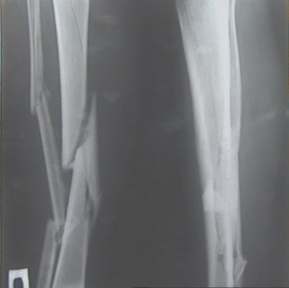

Александр Николаевич, к сожалению больной не является на контрольные осмотры. Я последний раз видел больного, когда прошло 7 месяцев после операции БОС. У него все хорошо. Каких либо жалоб и ограничений в нагрузке нет. Высылаю снимки до операции и последние снимки.